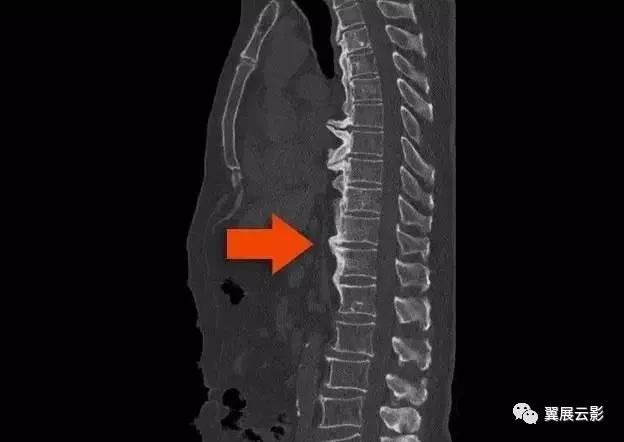

是一种以广泛异位骨化为主要病理改变的疾病,多发生在脊柱前纵韧带常累及后纵韧带、黄韧带,是不同于眷柱退行性改变的一种独立疾病。其中以脊柱病变最常见,胸椎最好发,其次是颈椎和腰椎,

Resnick提出的DISH影像学诊断标准包括:

1、4个以上相邻椎体前外侧缘流注样钙化或骨化;

2、受累椎体没有广泛椎间盘退行性病变,包括受累区椎间盘高度存在,没有真空现象;

3、缺乏上下关节突关节骨质硬化和骶髂关节骨质侵蚀、硬化或融合性病变。